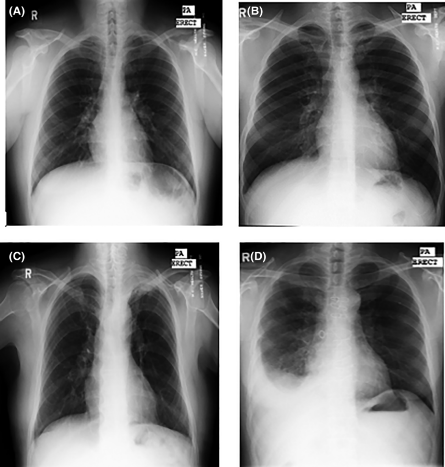

Деректер жинау – ашық интернет дерекқорларынан «сау өкпе» және «ауру өкпе» суреттерін таңдау;

Сау өкпе

Пневмониялы өкпе

Бұл зерттеу жұмысының барысында біз өкпе ауруларын, әсіресе пневмонияны анықтауда жасанды интеллектіні (ЖИ) қолданудың маңызын қарастырдық. Өкпенің сау және ауру түрлерінің рентген суреттерін салыстыру арқылы пневмонияның негізгі белгілерін айқындауға болады. Дәстүрлі әдістермен салыстырғанда ЖИ технологиясы дәрігерлерге уақытты үнемдеуге, диагнозды дәл қоюға және науқастарға дер кезінде көмек көрсетуге мүмкіндік береді.